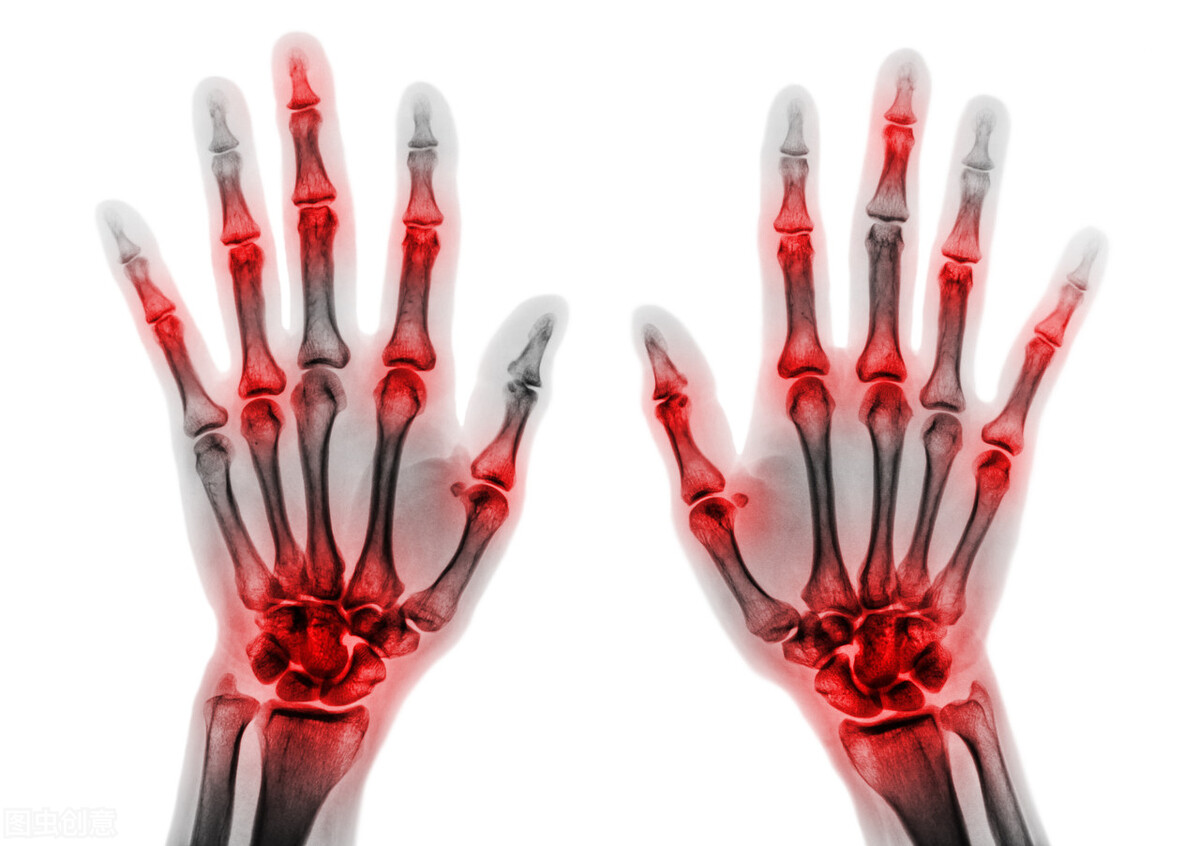

痛风是一种常见的并且非常复杂的关节炎类型的疾病,主要是因为身体内的嘌呤物质代谢异常所引起的,痛风发作的时候,可能会引起身体内的尿酸水平升高,患者的关节会出现红肿和疼痛,同时还可能会出现关节麻木和僵硬。严重的可能会出现关节变形,痛风发病比较急,一般持续几天或者几周不等,给患者的身体带来极大的痛苦,也给生活造成了很多麻烦,尤其是在饮食方面。